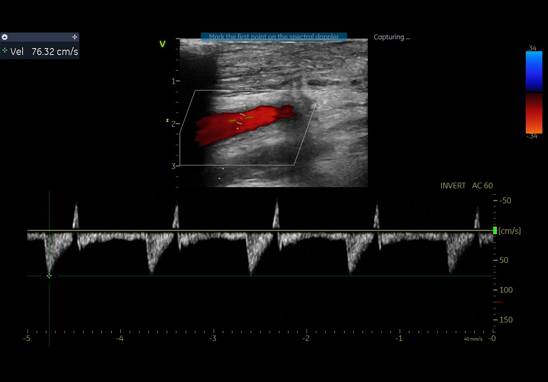

通过右肱动脉置入球囊,术中制造临时性Ⅰ型内漏,实现头臂干血流70%、左颈总动脉60%、左锁骨下动脉40%-50%的维持。